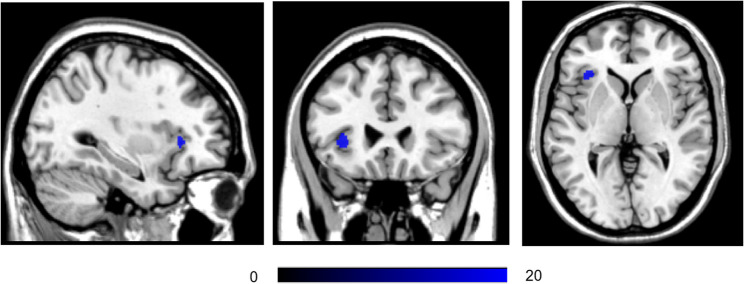

Results: The DYS, ND, and HC groups showed significant differences in grey matter volume in the left insula (pFDR =0.041). Compared to the HC group, both cerebral infarction groups (ND and DYS) demonstrated increased functional connectivity between the left insula and the left lateral occipital cortex (superior division), left precuneus, and left cerebellum. In contrast, functional connectivity with the right insula cortex, right frontal operculum cortex, left anterior cingulate, and right frontal pole was decreased. Among these differences, compared to the ND group, the DYS group showed a more significant reduction in functional connectivity within the right frontal operculum cortex and a more pronounced increase in functional connectivity within the left lateral occipital cortex superior division and left cerebellum. Compared to the HC group, patients in both cerebral infarction groups (ND and DYS) showed significantly enhanced functional connectivity between the right insula and the right posterior cingulate gyrus, left lateral occipital cortex (superior division), right precuneus, left frontal pole and right frontal pole. Conversely, functional connectivity with the left insula cortex and left anterior cingulate gyrus was significantly reduced. Moreover, compared to the ND group, the DYS group demonstrated more pronounced increases in functional connectivity within the right posterior cingulate gyrus and right superior cerebellar peduncle, along with a more significant decrease in functional connectivity within the right insula cortex. Enhanced FC between the left insula and the left lateral occipital cortex (superior division) correlated positively with PAS, while enhanced FC between the right insula and the right cerebellum correlated negatively with PAS.

Conclusion: Our study found left insular gray matter atrophy underlies the pathology of PSD, and abnormal insular functional connectivity is key to its development. The severity of post-stroke dysphagia can affect the functional connectivity between the insula and the right cerebellum as well as the left occipital lobe. These results reveal potential neural compensation mechanisms in PSD and offer new directions for clinical prognostic biomarker development.